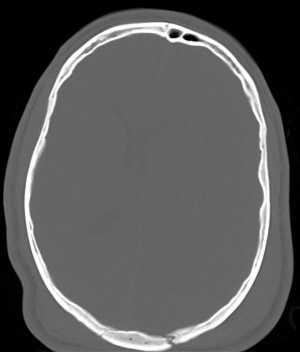

| This head CT scan in axial view is taken in "bone window" exposure which provides detail of the skull, but makes the intracranial contents appear blank. In this view can be seen a skull fracture as a consequence of the trauma that led to a subdural hematoma. |